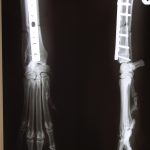

2. TPLO anstellen des Tibiaplateaus mit einer Osteotomie und Einbringen einer Spezialplatte.

Osteosynthese: